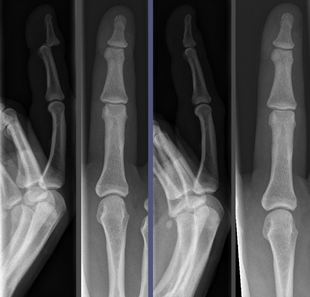

Joint dislocation in the DIP of the third finger before (left images) and after (right images) reduction. |

Once the fragments are reduced, the reduction is maintained by application of casts, traction, or held by plates, screws, or other implants, which may in turn be external or internal. It is very important to verify the accuracy of reduction by clinical tests and X-ray, especially in the case of joint dislocations.